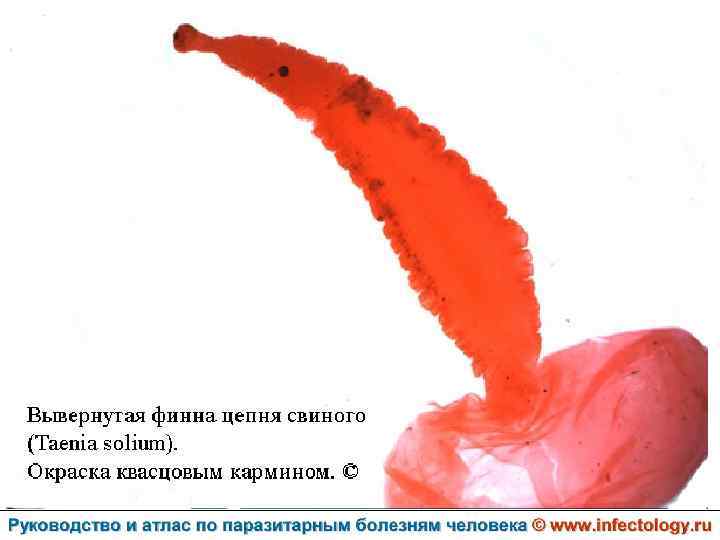

Цистицеркоз (шифр по МКБ 10 - B 69) – биогельминтоз, который вызывается паразитированием в тканях и органах человека и животных личиночной стадии цепня вооруженного – цистицерка (Cysticercus cellulosae) Болезнь проявляется разнообразными симптомами в зависимости от локализации цистицерков.